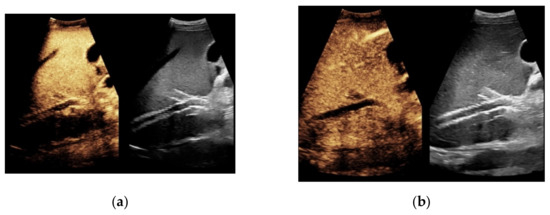

Figure 7. 52-year-old female patient with irregular presentation of the transjugular intrahepatic portosystemic shunt (TIPS) on B-mode ultrasound (a) and partial flow on Color Doppler ultrasound (CDUS) (b). After contrast administration, in contrast to CDUS, regular and continuous contrast of the TIPS is seen without evidence of thrombotic alterations or occlusion (c).